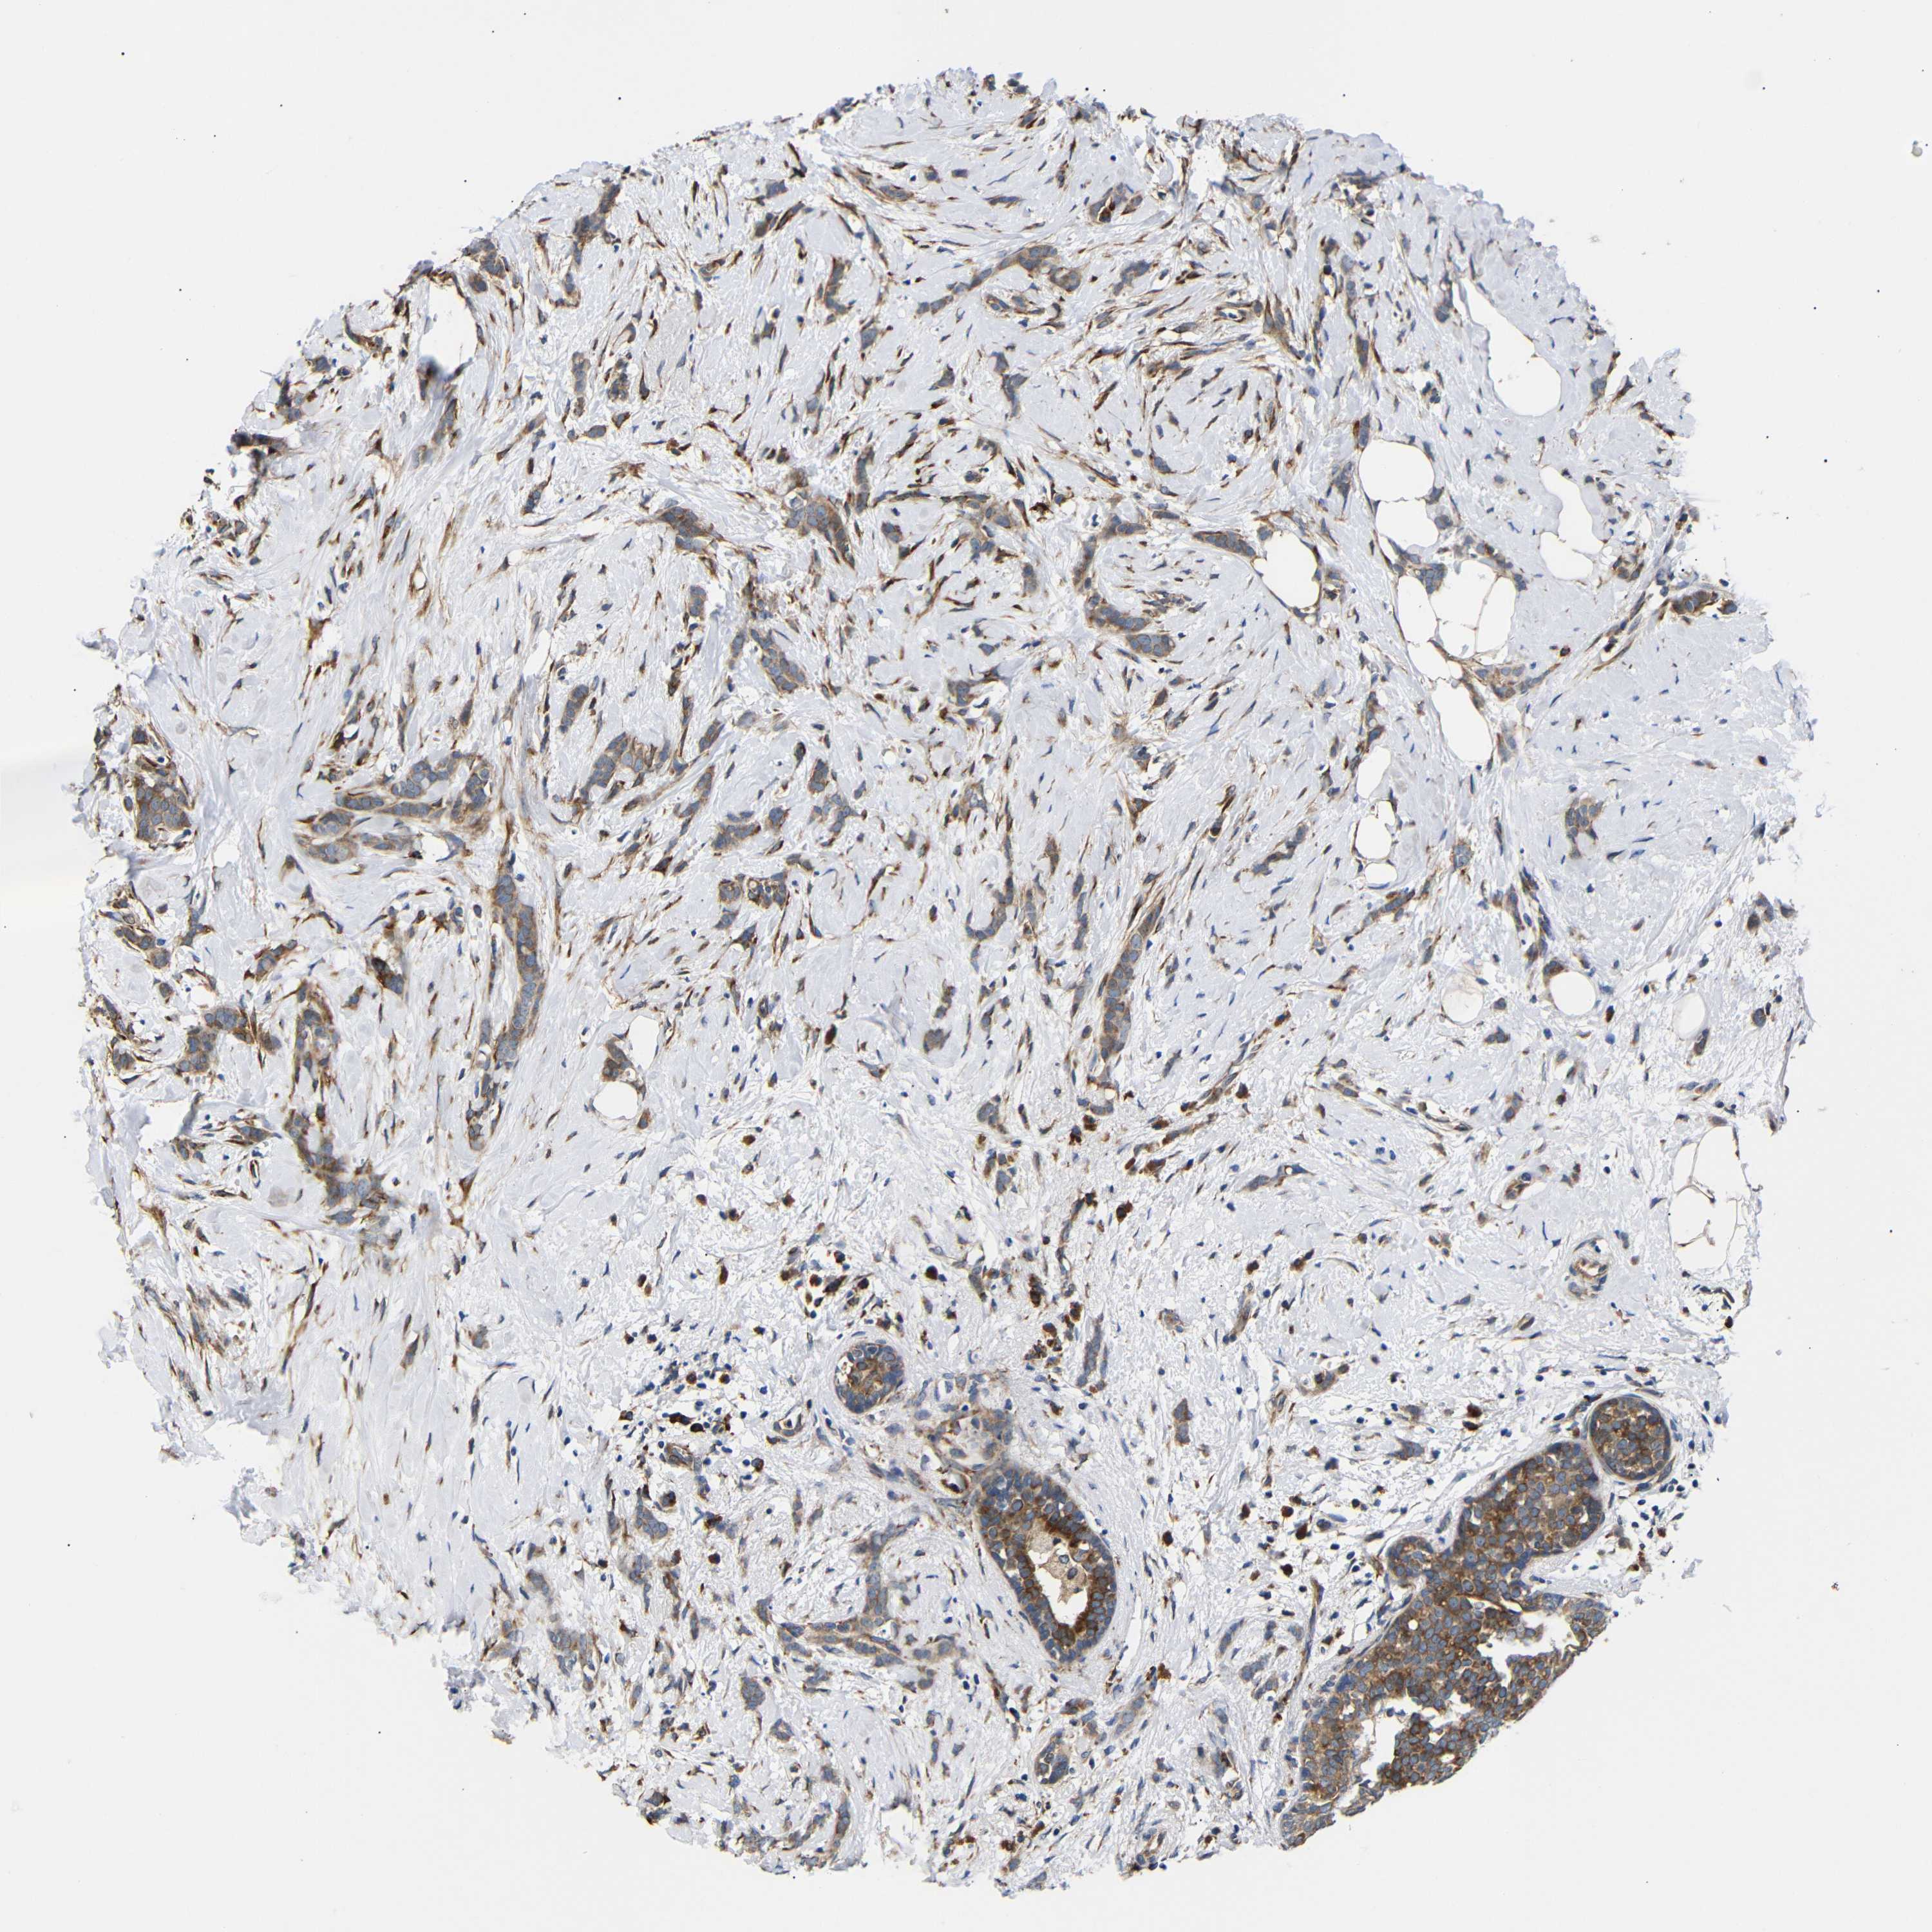

BRCA TCGA BRCA VALIDATION PROTEIN EXPRESSION

Breast cancer

Human cancer

Breast invasive carcinoma